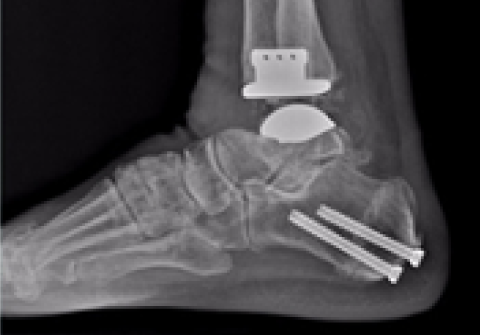

발목 인공관절 수술

2016.11.01

2017.02.01